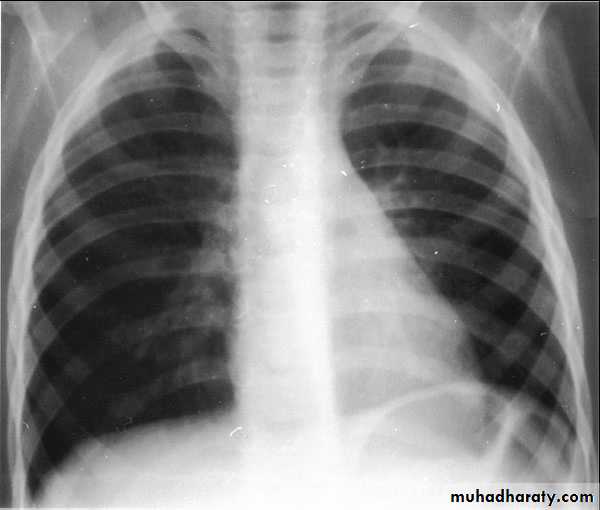

Q 10/ A previously healthy 2-year-old black child has developed a chronic cough during the previous 6 weeks. He has been seen in different emergency rooms on two occasions during this period and has been placed on antibiotics for pneumonia. Upon auscultation, you hear normal breath sounds on the left. On the right side, you hear decreased air movement during inspiration but none upon expiration. Inspiratory (A) and expiratory (B) radiographs of the chest are shown below. Which of the following is the most appropriate next step in making the diagnosis in this patient?

A

B

Recurrent pneumonias in an otherwise healthy child should suggest the potential for anatomic blockage of an airway. In the patient in this question, the findings on clinical examination suggest a foreign body in the airway. Inspiratory and expiratory films can be helpful. Routine inspiratory films are likely to appear normal or near normal (as outlined in the question and noted in the first radiograph). Expiratory films will identify air trapping behind the foreign body (as noted on the second radiograph). It is uncommon for the foreign body to be visible on the plain radiograph; a high index of suspicion is necessary to make the diagnosis. Suspected foreign bodies in the airway are potentially diagnosed with fluoroscopy, but rigid bronchoscopy is not only diagnostic but also the treatment of choice for removal of the foreign body.